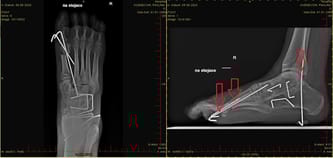

Operacja przebiegła pomyślnie! Wszystkie palce udało się wyprostować wraz z paluchem, który wymagał przemieszczenia kości śródstopia. Ścięgno Achillesa zostało wydłużone. Jednak czy w pełni udało nam się osiągnąć cel, będziemy mogli stwierdzić dopiero po zakończeniu rehabilitacji...

Dzięki operacji stopa zdecydowanie wygląda lepiej. Teraz przód jej zostanie odciążony i będę w końcu używać przy stawianiu stopy pięty – przez 32 lata było to niemożliwe!

Swoją pierwszą operację przeszłam w wieku 7 lat. Kolejna potrzebna była już 2 lata później. Mimo przebytych zabiegów kości stopy uległy dużej deformacji. Zniekształcenie końsko-szpotawe jest złożoną wadą układu mięśniowo-szkieletowego. Mając 16 lat, po raz kolejny trafiłam do szpitala. Korekcja znów nie dała oczekiwanych rezultatów.

Po ostatniej operacji pierwszy raz od kiedy pamiętam, mogłam w minimalnym stopniu poruszać stopą. Jednak przykurcz ścięgna Achillesa nadal nie pozwala mi na podniesienie stopy w górę.

Po latach poszukiwań specjalisty trafiłam do kliniki ortopedycznej w Poznaniu. Po konsultacji lekarze chcą podjąć się kolejnej operacji, która ma polegać m.in. na wydłużeniu ścięgna Achillesa oraz korekcie zdeformowanych palców.